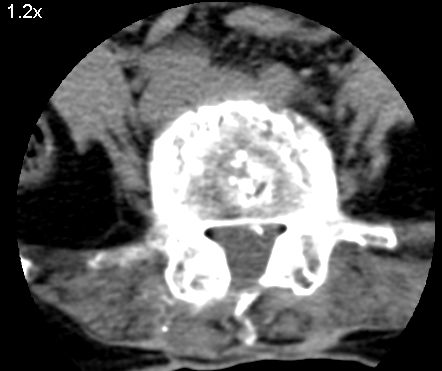

以下是引用余辉在2007-9-4 21:00:00的发言:[br]椎体棘突有点异常(像是被切割了),不知有否手术史,如椎体融合术等。单纯的退行性变可以出现椎间隙变窄,但同时一般会出现椎体上下缘的硬化增生,且椎体间完全融合的机率更小,本例椎体完全融合且椎体上下皮质缘破坏掉了,如果没有手术史,就应该考虑椎间盘炎性病变了,且椎体棘突及棘间韧带的变化也并不是不支持这个,多数小关节也融合了,且其形态也容易让人联想到如强脊炎及类风关等病变。[br][br][本贴已被 余辉 于 2007-9-4 21:03:55 修改过]

以下是引用chry3在2007-9-4 20:42:00的发言:[br]椎间盘病史?是什么样的病史,无双下肢放射痛,那就不是椎间盘突出了。是感染、什么性质的?[br]从图象看椎间隙消失,椎间盘组织未见,锥体滑脱是因为椎间盘溶解造成的[br]l4、5椎体骨质结构未见异常,l5上缘是l4的长期压迫所致[br]还是考虑椎间盘感染,结核。[br]